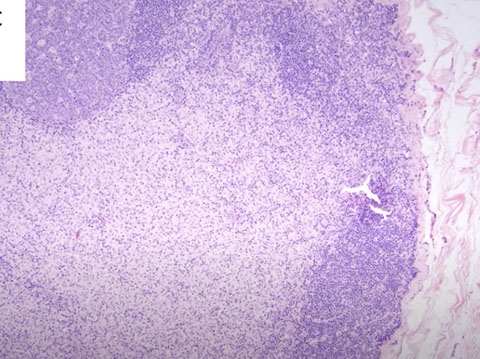

Infectious mononucleosis with areas of preserved architecture with reactive follicles, patent subcapsular sinuses, and intact capsules. Despite relative hyperplasia of paracortex, always has areas of preserved normal architecture

Infectious mononucleosis. Admixed population of cells of varying sizes. In areas where immunoblasts predominated (right) which could be a florid expansions, like large aggregates or sheets of cells with mitotic activity. Spend some time on low power to appreciate the normal architecture, try to find areas with a variety of cell types. Immunoblasts may resemble Reed-Sternberg (RS) cells (inset). [3]